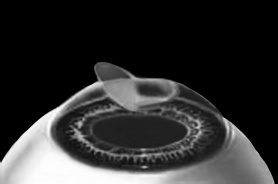

После формирования роговичного лоскута убирают инструменты микрокератома, затем шпателем откидывают его вбок (рис. 5). Обнажается роговичное ложе, то есть место, на котором лежал лоскут. Это верхние слои стромы роговицы. Ложе осушают тупфером и так же, как и при ФРК, настраивают лазер и испаряют несколько микрон вещества стромы (рис. 6). Потом промывают строму водой и шпателем укладывают лоскут на место.

Рис. 5. Роговичный лоскут откинут в сторону.

Иллюстрация с сайта Международного лазерного центра www.optics.ru